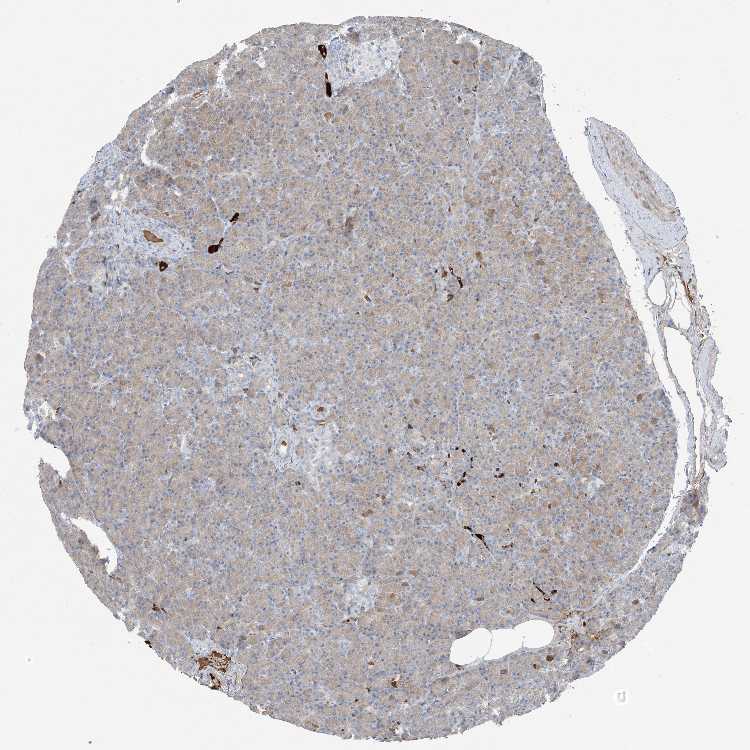

PANCREAS - Antibody stainingi

Antibody staining in the annotated cell types in the current human tissue is reported as not detected, low, medium, or high, based on conventional immunohistochemistry profiling in selected tissues. This score is based on the combination of the staining intensity and fraction of stained cells.

Each image is clickable and will lead to virtual microscopy that enables deeper exploration of all samples and also displays staining intensity scores, fraction scores and subcellular localization as well as patient and tissue information for each sample.

Antibody HPA009134

Exocrine glandular cells Low

Pancreatic endocrine cells Not detected